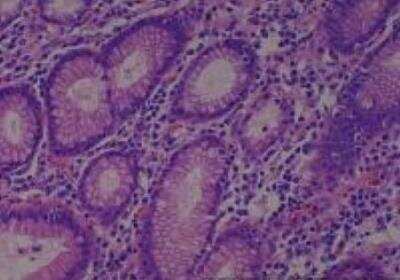

Hematoxylin & Eosin Stain: Human Common Tissue MicroArray (Normal Adjacent) [NBP2-30215] - 103. Stomach